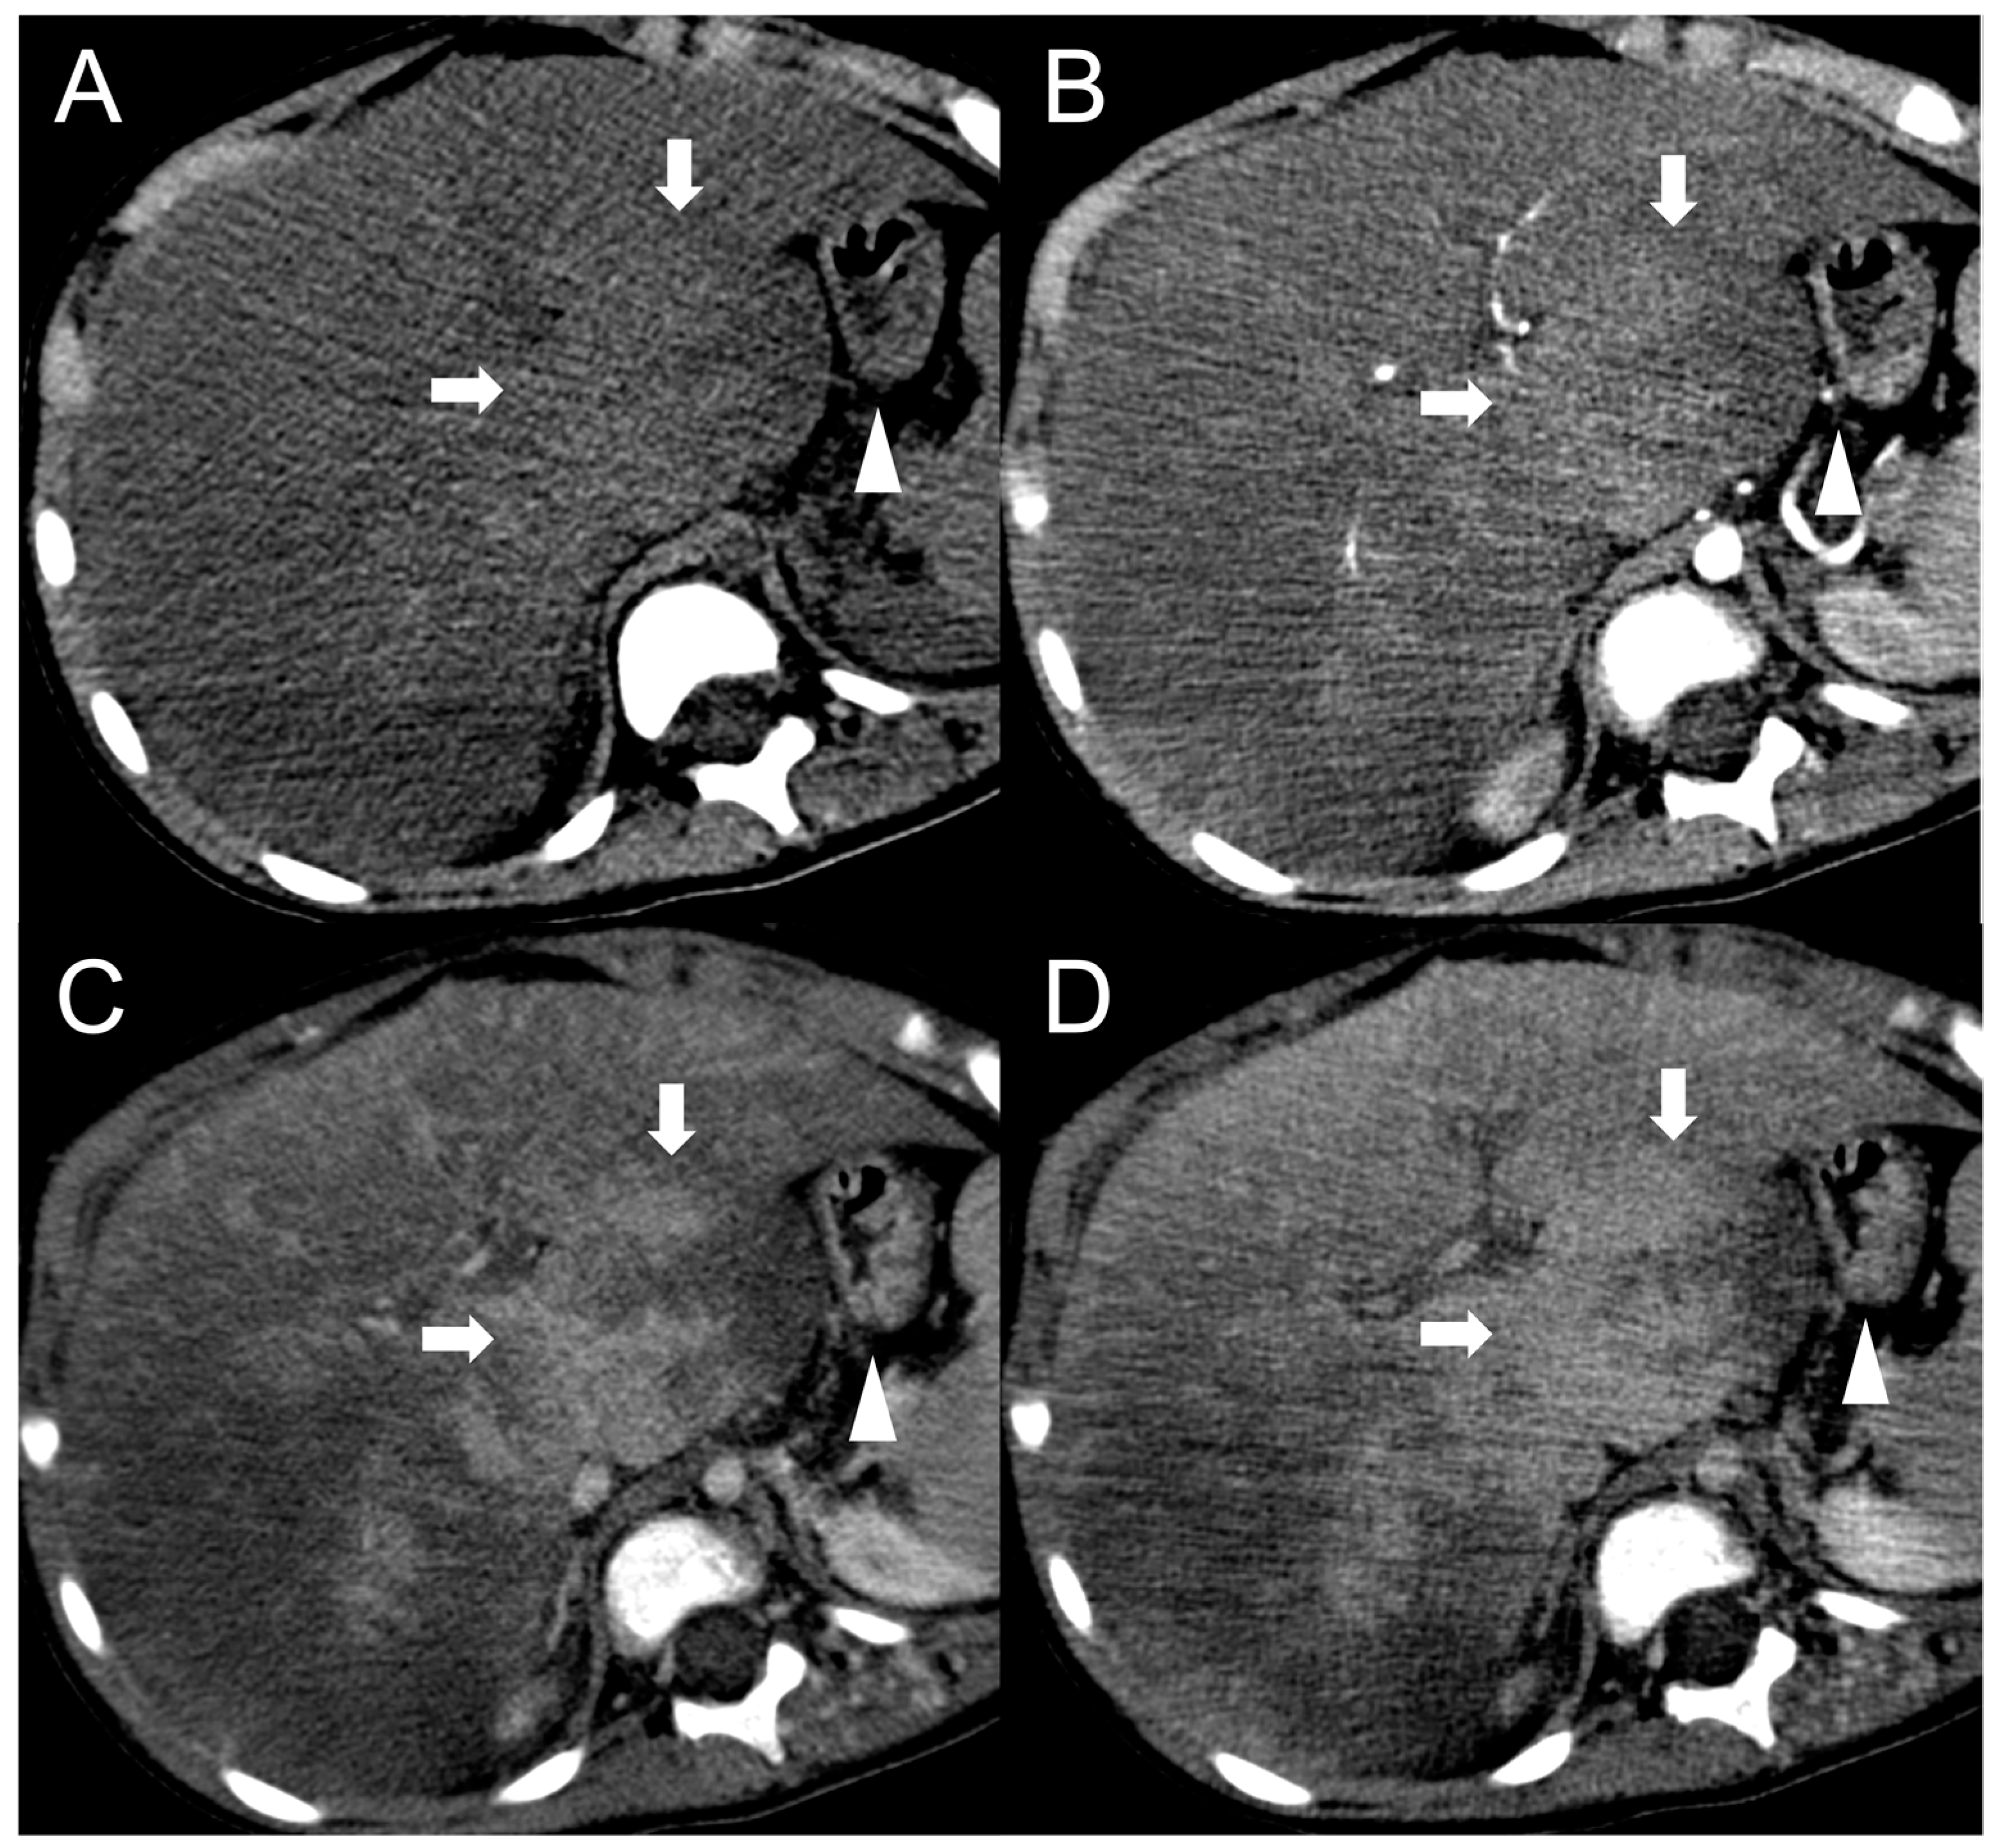

Figure 8.

CT examination of a 5-year-old female patient with Budd–Chiari syndrome revealing a pseudo-lesion caused by hypertrophy of the caudate lobe. The caudate lobe (arrows) shows slight hyperdensity on unenhanced images (A), with heterogeneous contrast enhancement in the arterial (B), portal (C) and delayed phase (D). Notably, this represents a normal enhancement pattern due to preserved venous drainage, in contrast to the surrounding congested liver parenchyma. The hypertrophied caudate lobe also causes compression on the stomach (arrowheads), contributing to its mass-like appearance.

Figure 9.

CT examination of a 5-year-old female patient with Budd–Chiari syndrome. Unenhanced (A) and arterial phase (B) images show diffuse inhomogeneity of the liver parenchyma. In the portal phase (C) a patchy “mosaic pattern” enhancement is observed, with ill-defined nodular pseudo-lesions. In the delayed phase (D), these lesions tend to merge and disappear, indicating their perfusion-related nature.